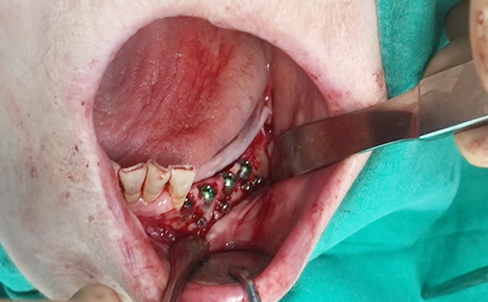

Simultaenous bone grafting for implants

Simultaneous bone graft and implant placement